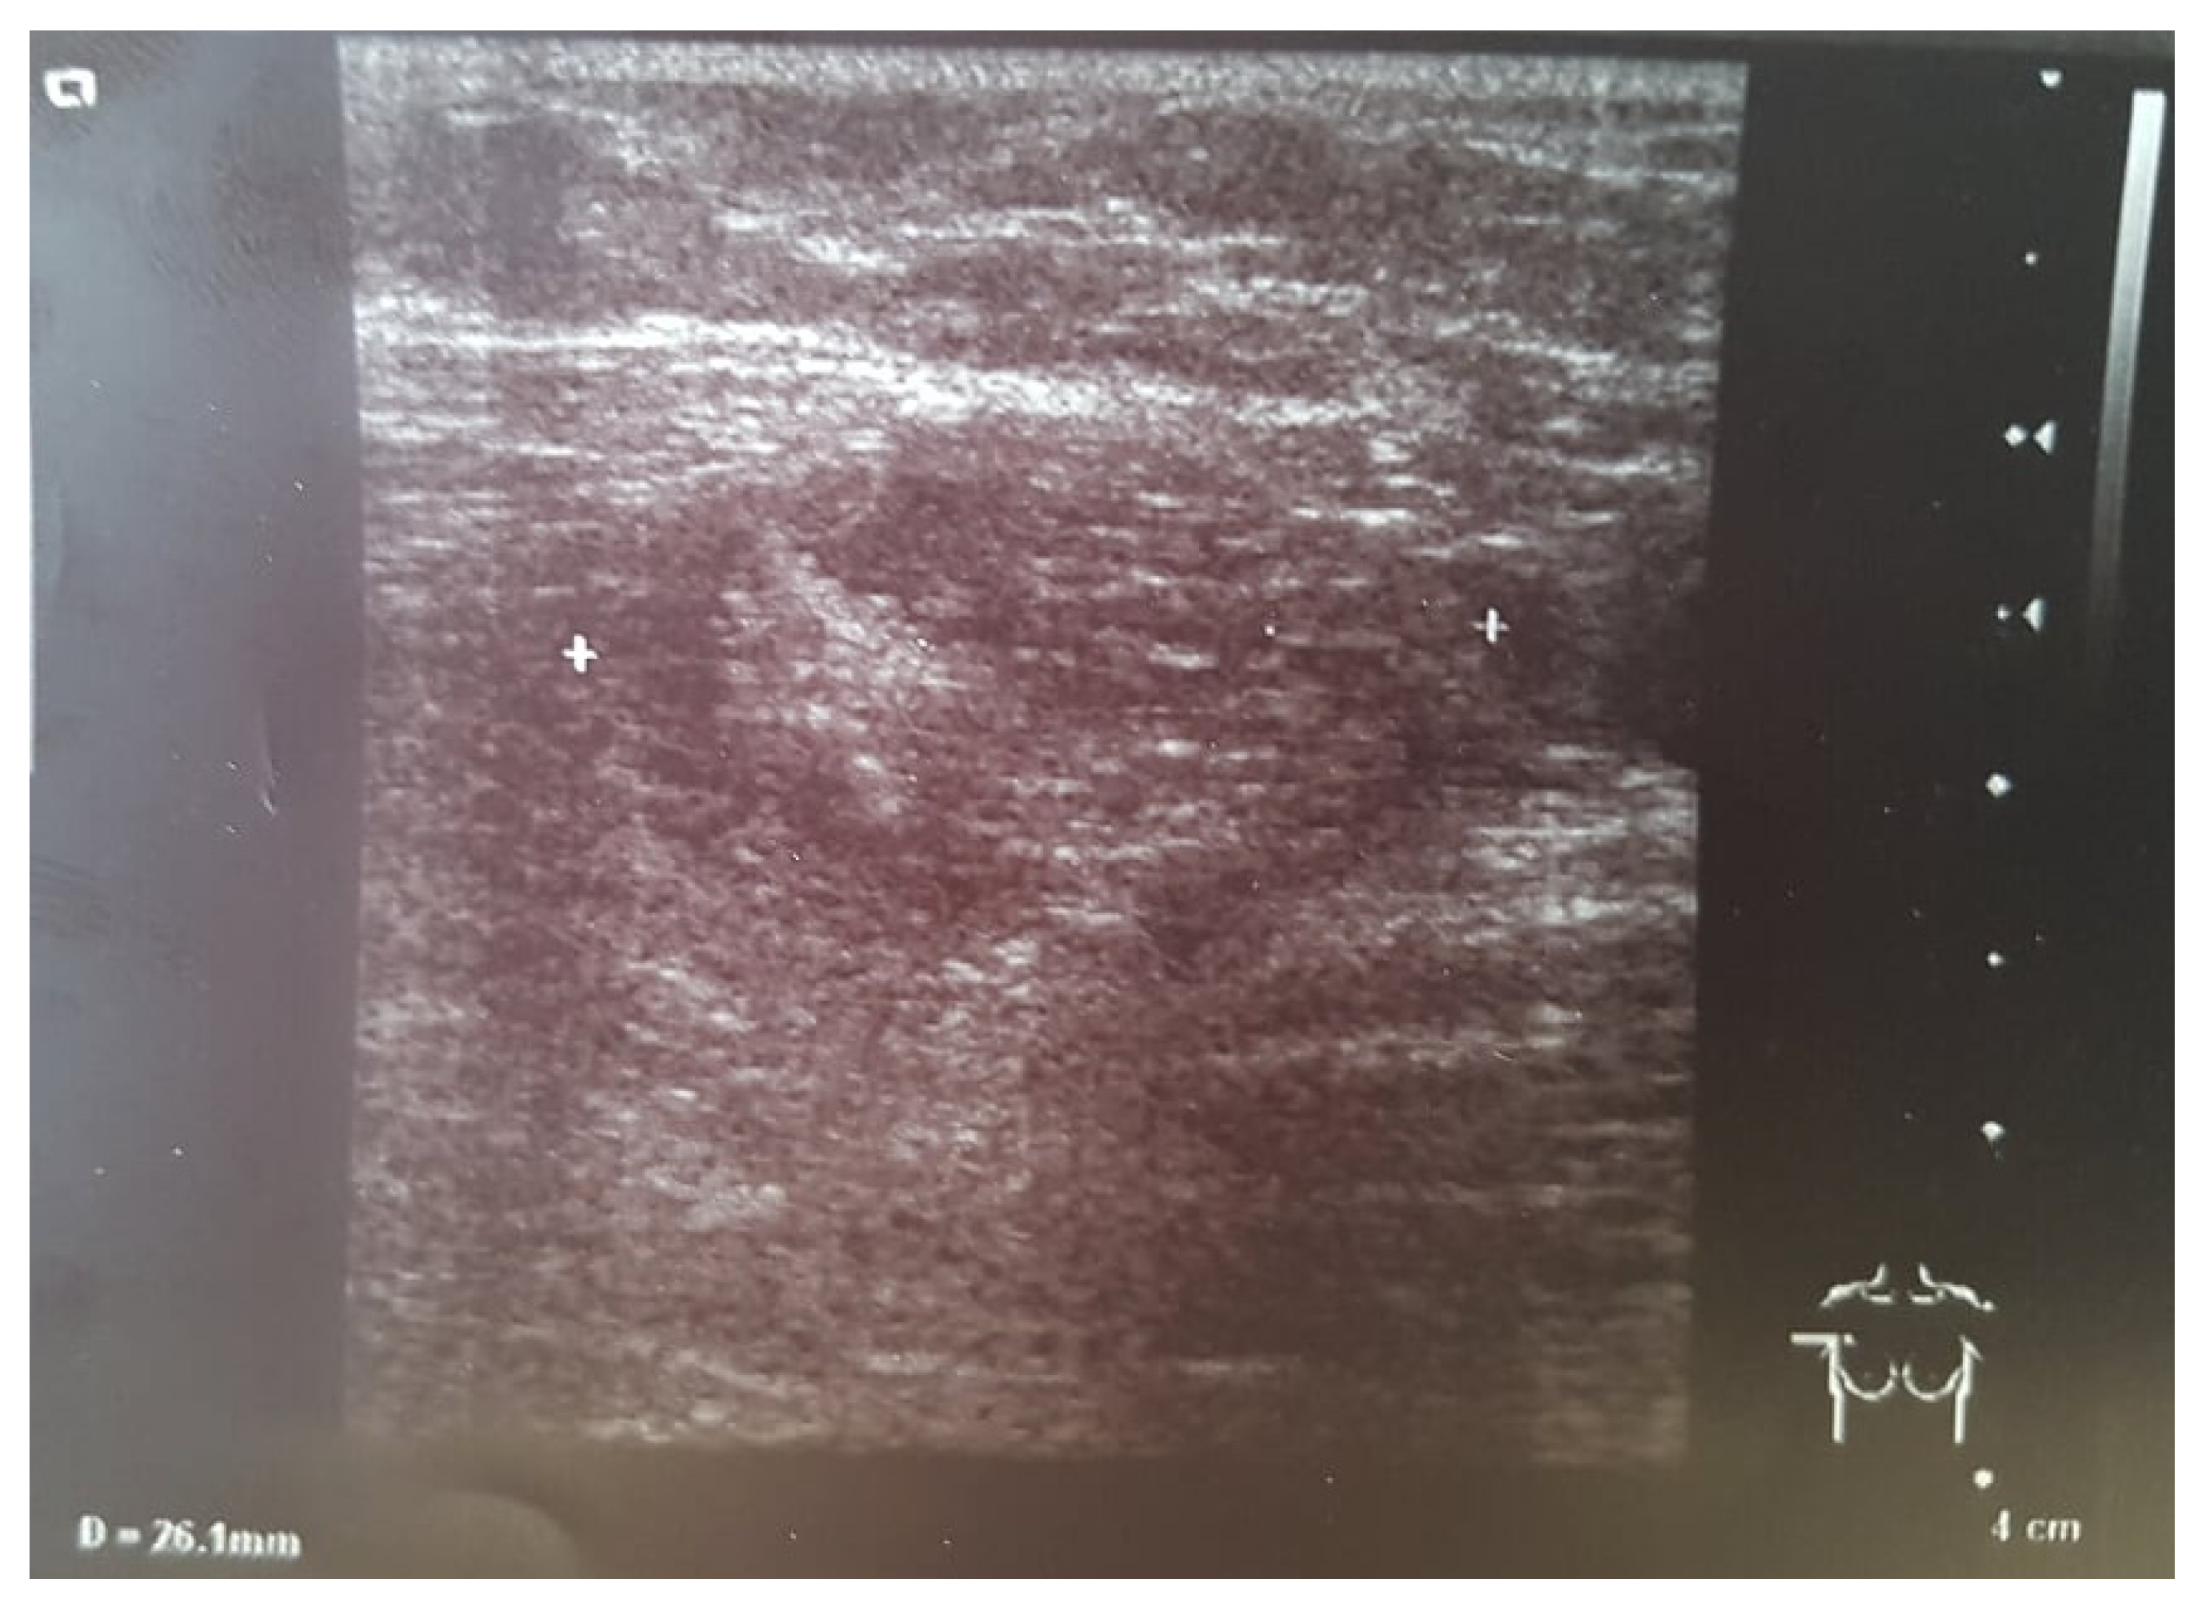

During ultrasonography (USG) behind the right nipple, a thick-walled cyst with polycyclic contours measuring 25 mm × 14 mm was diagnosed. The lesion communicated with the dilated milk duct and the right retracted nipple. The left breast was normal. In both armpits, enlarged lymph nodes up to 20 mm were found (Figure 2).

The most crucial element of diagnostics, also in an abscess, is physical examination [6,7,8]. The differential diagnosis between benign or malignant breast mass, inflammatory breast cancer, and cellulitis should always be performed [4,7,8]. Leukocytosis and an increase in CRP levels can occur in any of the diseases mentioned above. In an ultrasound examination, abscesses can be observed as ill-defined masses with internal septations [7]. A breast cancer tumor is often seen as hypoechoic with irregular borders and may appear spiculated. Other ultrasound features suggesting breast cancer include non-parallel orientation (not parallel to the skin), a mass that is taller than wide, acoustic shadowing (a finding that indicates a solid mass), microlobulation (collections of small lobes), duct extension, a branching pattern, a mass within a cyst, and angular margins (an irregular or jagged appearance) [9]. Acoustic shadowing and angular margins were observed in our patient. The ultrasound specialist was also concerned about the solid element of the lesion coexisting with the cystic part.

Figure 2. USG examination of the right breast. White characters indicate the range of the lesion.